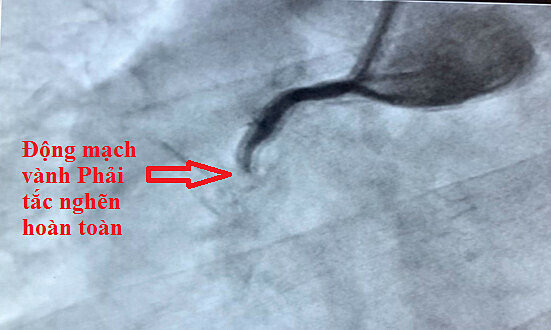

Một ngày sau, một người đàn ông 64 tuổi khác ở quận 6 đột nhiên bị ngắn họng khi ngủ và đau họng bên trái, phải ngồi dậy thở. Ông có tiền sử tăng huyết áp, đái tháo đường týp 2, rối loạn mỡ máu và hút thuốc nhiều. – “Tại thời điểm nhập viện, cả hai bệnh nhân đều bị đau ngực dữ dội, vã mồ hôi và huyết áp cao. Nhịp tim thấp và nguy hiểm đến tính mạng”, bác sĩ He Dongtian, trưởng khoa tim mạch của Ruan Trai cho biết. Bệnh viện. Bác sĩ chẩn đoán nhồi máu cơ tim cấp và tắc nghẽn tim. Động mạch vành.

Hai bệnh nhân được tiến hành thông tim để nối lại động mạch vành bị tắc nghẽn, giúp giảm đau tức ngực, mạch và ổn định huyết áp. Tiến sĩ, bác sĩ phân tích rằng: “Cả hai đều được cứu sống nhờ can thiệp mạch vành kịp thời”